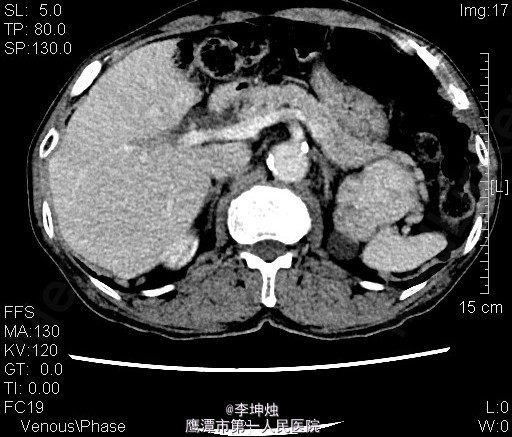

3、查体:增加腹压或站立位时右侧腹股沟隆起,可触及一大小约4*5cm肿物,可进入同侧阴囊,质软,边界清,无压痛,压迫肿物表面后嘱患者咳嗽,有冲击感,平卧或用手可将肿物回纳腹腔。直肠指检:肛门括约肌稍松弛,前列腺明显增大,大小约:3×4cm,表面光滑,质韧,边缘清楚,中央沟变浅,未触及明显结节,指套未见染血。 4、辅助检查:当地人民医院,腹部CT提示考虑左肾Ca可能;慢性膀胱炎;右侧腹股沟区见肠管嵌如;前列腺增生。我院双肾CT平扫+增强:左肾上极肿块,考虑肾癌,侵犯左肾上部皮髓质及左肾上盏,可疑侵及胰尾部。

5、诊断:左肾占位,左肾ca? 6、处理:入院完善相关检查,核素肾动态显像:双肾灌注轻度降低、功能中度受损。双肾+肾上腺CT:左肾上极肿块,考虑肾癌,侵犯左肾上部皮髓质及左肾上盏,可疑侵及胰尾部。排除手术禁忌后,行“腹腔镜下左肾根治+肾门淋巴结清扫术”,术后予“头孢哌酮钠舒巴坦钠(舒普深)”抗感染、抑酸、营养补液等处理,术后恢复可。病理提示嗜酸性细胞瘤。

7、肾嗜酸细胞瘤病因目前不明确,患病年龄与肾透明细胞癌相似,影响学结果相似,大多数患者的影像学检查结果很难与肾透明细胞癌相区别,由于部分患者肿瘤中央部有放射状疤,可以通过CT或MRI检查发现肿瘤中央星状瘢痕可为诊断本病提供帮助。确诊需依靠手术后病理检查。怀疑是肾嗜酸细胞瘤时,肿瘤大小和部位不影响保留肾单位手术,但由于术前多数患者不能被明确诊断,往往被误诊为肾癌而实施了根治性肾切除术。